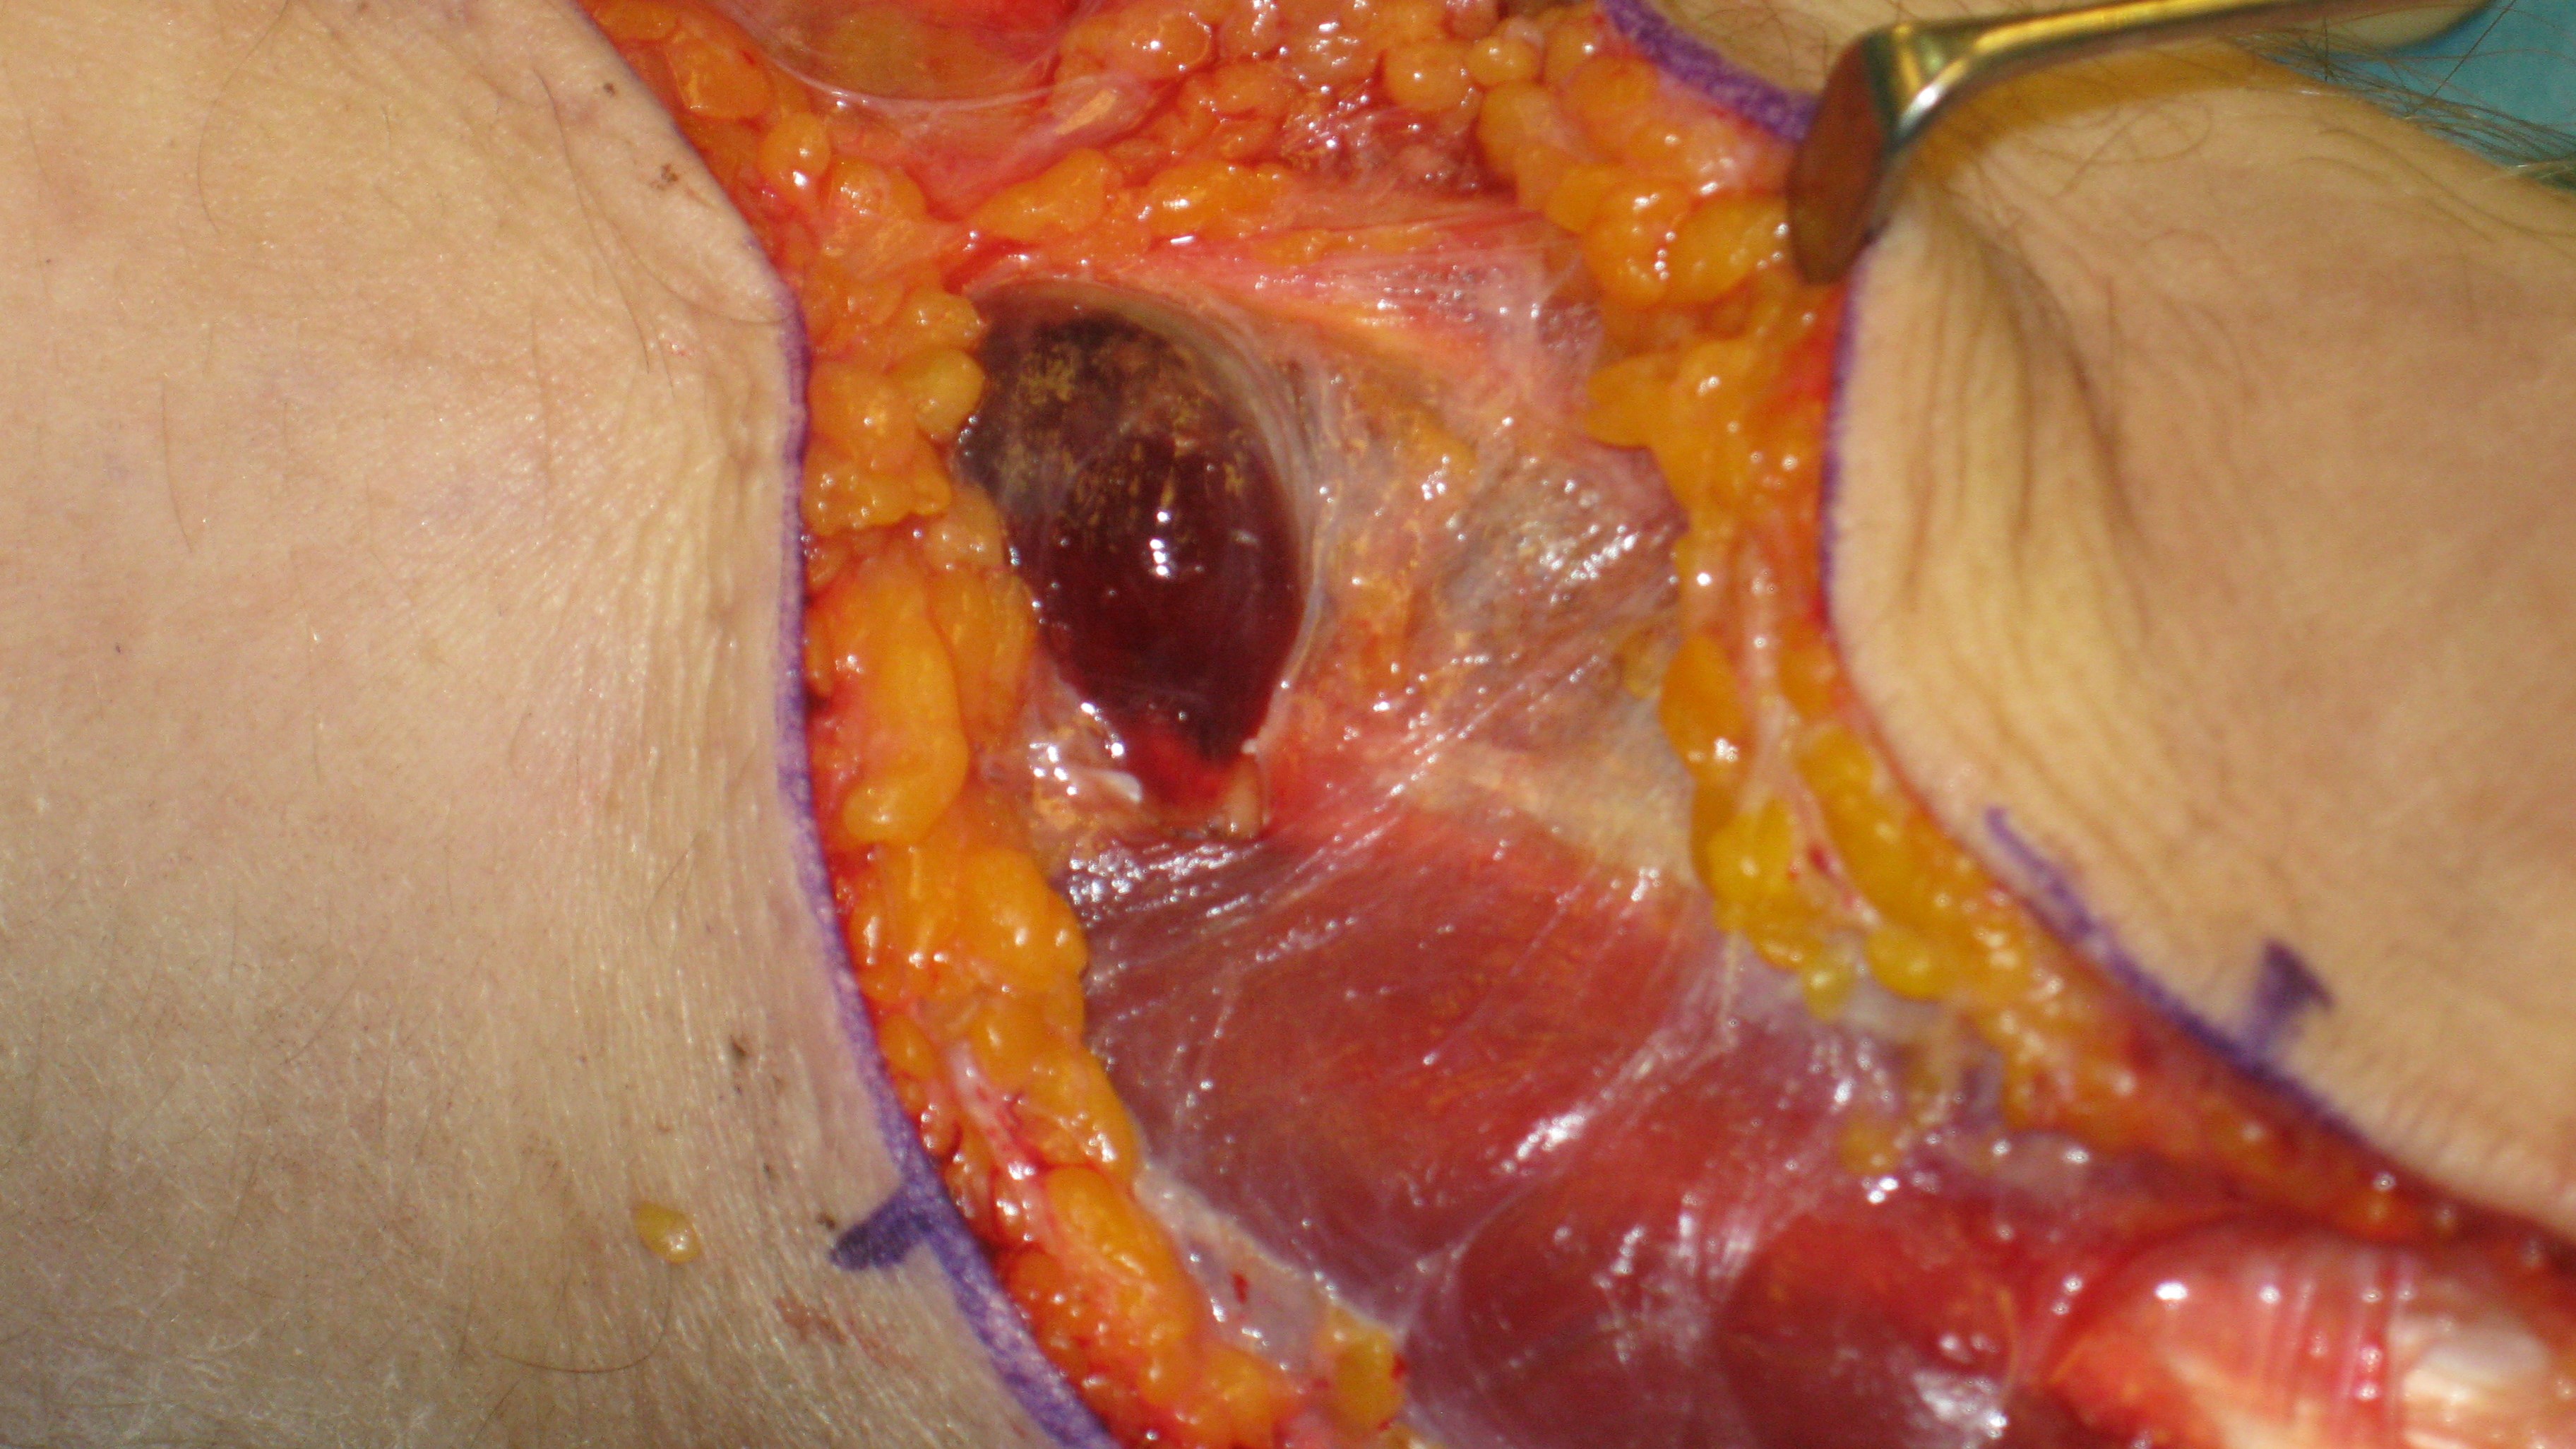

Behandling

Behandlingen är att det avgränsade rummets väggar, dvs. att fascior öppnas kirurgiskt. Många gånger sväller då musklerna fram och huden kan inte slutas. Man får då dra ihop såret så gått det går utan för mycket spänning för att sedan sluta såret när musklerna svällt av. Det finns även teknik för att hålla ihop och successivt sluta sårkanterna mha av ståltråd eller elastiska band.

Hudtransplantat kan senare behövas. När det gäller underarmen finns tre kompartment och både extensor och flexormuskulatur kan drabbas. I handen finns ett tiotal slutna kompartment som alla måste öppnas kirurgiskt om kompartment syndrom misstänks i denna region.